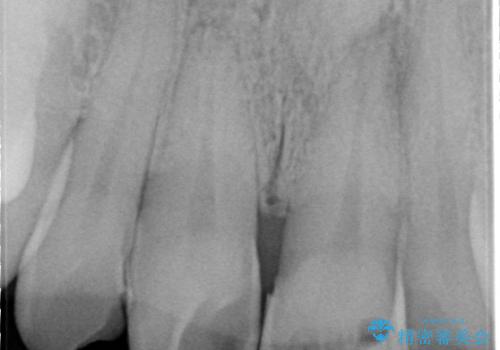

- かけてしまった前歯をきれいにしたいとのことで来院されました。

レントゲンを撮影すると、根の神経の治療が必要なことがわかりました。

根管治療を行いセラミックを装着する計画としました。